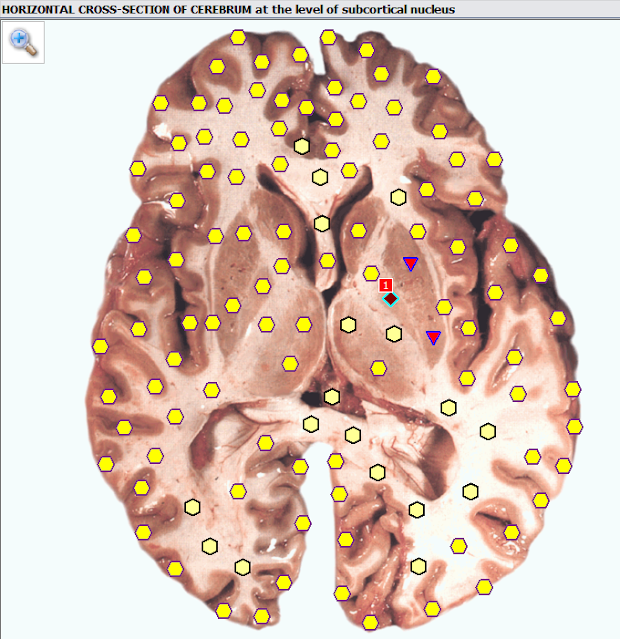

Δείτε παρακάτω περιστατικό, όπου μέσω ειδικού υπολογιστικού συστήματος, σε άνδρα ηλικίας 69 χρόνων με συμπτωματολογία τρόμου κυρίως σε δάκτυλα του χεριού, ανιχνεύεται στον εγκέφαλο και ειδικότερα στο ύψος των βασικών πυρήνων διαταραχή, της οποίας η πιο λεπτομερής ανάλυση οδηγεί στη αποκάλυψη νόσου του Πάρκινσον, η οποία και αποκαθίσταται με σχετική παρέμβαση, μέσω του ιδίου συστήματος.